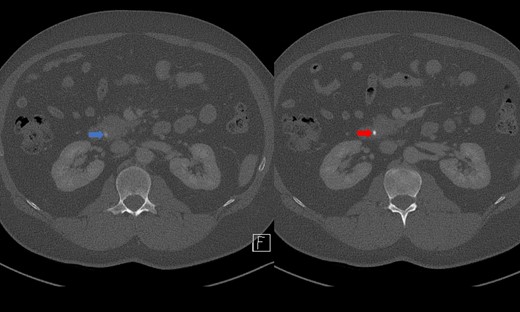

Portal venous contrast enhanced computed tomography (CT) of the abdomen revealed a layered dependent hyperattenuating material within the biliary tree (Fig. 1). The common bile duct (CBD) was dilated measuring 7.5 mm in diameter and filled along its course with radiodense material. Mild distention of the cystic duct and intrahepatic biliary tree were also noted with a 4 mm calculus in the CBD at the level of the duodenal ampulla (Fig. 2). There was no radiological evidence of cholecystitis.

Contrast-enhanced CT demonstrating limy bile within the gallbladder neck (left image) and CBD (right image).